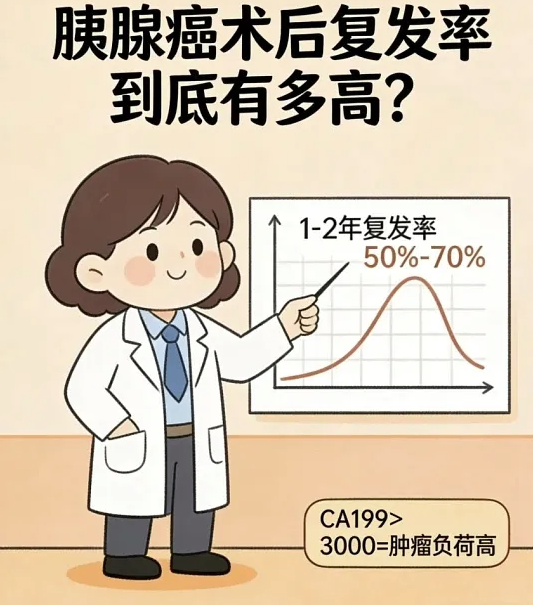

胰腺癌:“癌中之王”,复发率超八成

胰腺癌位置深、早期难发现,能做手术的患者本来就少。就算手术成功,复发率也在 80% 以上,多数患者术后 6 到 12 个月就会局部复发或肝转移。

这种癌的癌细胞侵袭性特别强,容易侵犯血管和神经,手术很难切干净。术后一定要严格遵医嘱做辅助化疗,密切关注 CA19-9 这个指标,一旦持续升高,就要警惕复发。